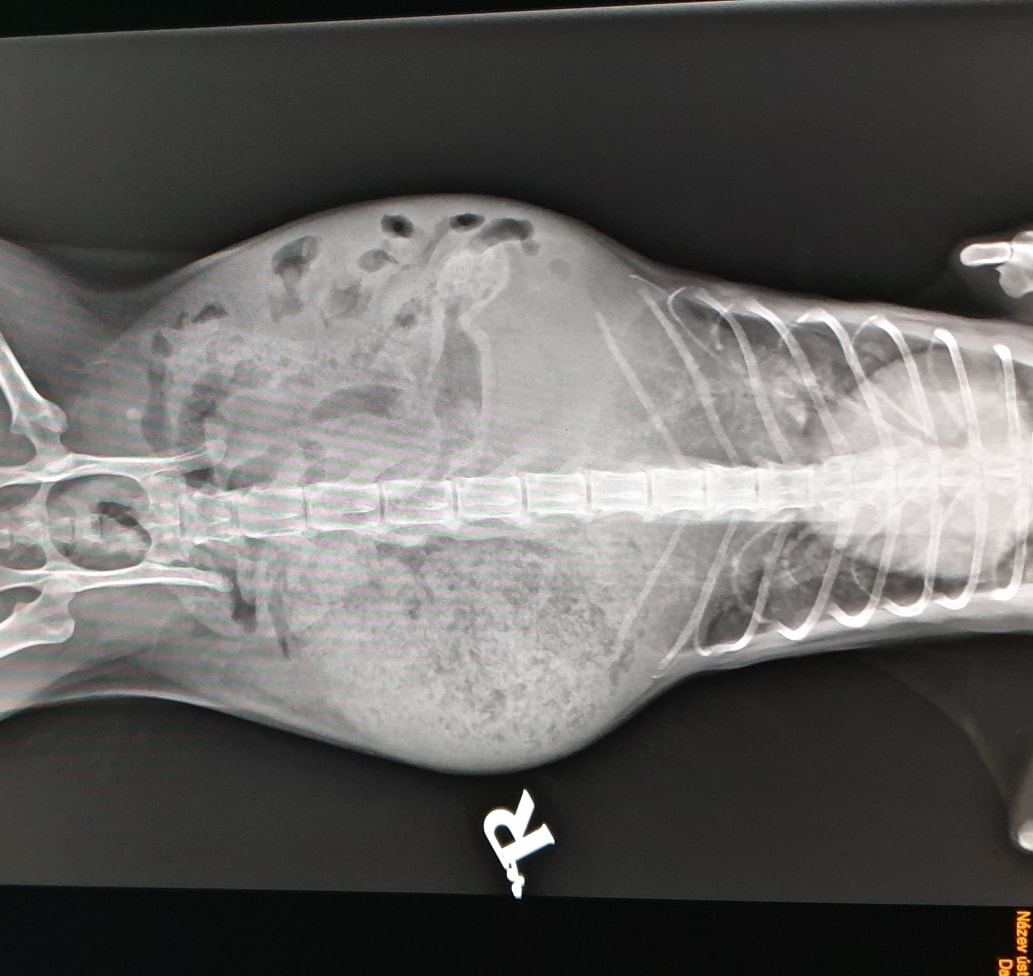

🔸Tam na nás již čekali. Pohotovostní službu měla paní doktorka ošetřující i Wariora. Nejprve několik RTG, sono a krev. Neznámá tekutina v břišní dutině, potíže s dýcháním, nic zlomeného. Obrovské srdce, vnitřní orgány zastřené. Zvláštní útvar v dutině břišní. Kočička byla dána na kyslík. A čekali jsme na stabilizaci. Podařilo se provést punkci a odebrat vzorek tekutiny. Pozdě večer se stav stabilizoval a dohodli jsme se na operaci – otevření. Operace byla dlouhá a zkončila pozdě v noci.